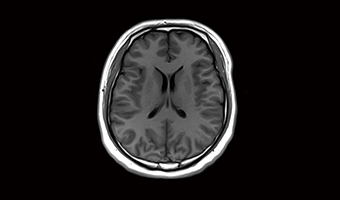

Beyin SWI’si 4-8x hızlanma elde edebilmektedir.

i-Smooth Sessiz Teknolojisi